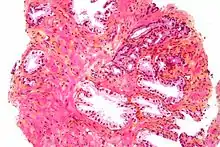

Microanatomy

The prostate consists of glandular and connective tissue.[3] Tall column-shaped cells form the lining (the epithelium) of the glands.[3] These form one layer or may be pseudostratified.[5] The epithelium is highly variable and areas of low cuboidal or flat cells can also be present, with transitional epithelium in the outer regions of the longer ducts.[11] The glands are formed as many follicles, which drain into canals and subsequently 12–20 main ducts, These in turn drain into the urethra as it passes through the prostate.[5] There are also a small amount of flat cells, which sit next to the basement membranes of glands, and act as stem cells.[3]

The connective tissue of the prostate is made up of fibrous tissue and smooth muscle.[3] The fibrous tissue separates the gland into lobules.[3] It also sits between the glands and is composed of randomly orientated smooth-muscle bundles that are continuous with the bladder.[12]

Over time, thickened secretions called corpora amylacea accumulate in the gland.[3]

Microscopic glands of the prostate